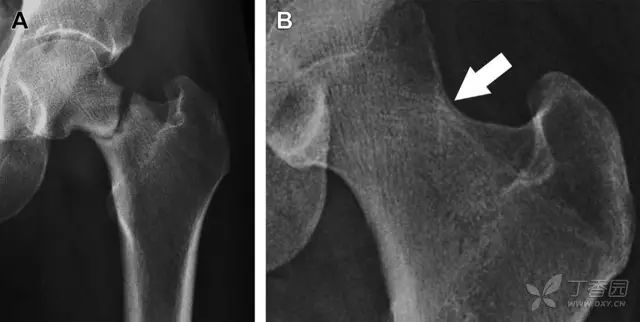

髋臼骨折最常见的类型是髋臼后壁骨折,几乎占髋关节骨折的 1/4,且常常合并髋关节后脱位。由于骨性结构重叠,可能肉眼看上去觉得非常轻微的骨折,事实却并非如此。髋臼后缘中断常常是髋臼后壁骨折的一个特征(图 2)。

图 2 为髋臼后壁骨折伴髋关节脱位患者。A 右侧髋关节 X 线片示股骨头后方可见一骨折线(箭头),髋臼后缘中断。B 左侧髋关节 X 片对照可见髋臼后缘连续(箭头)。C CT 三维重建图像示髋臼后壁缺损,可见旋转、移位的骨折块(箭头)